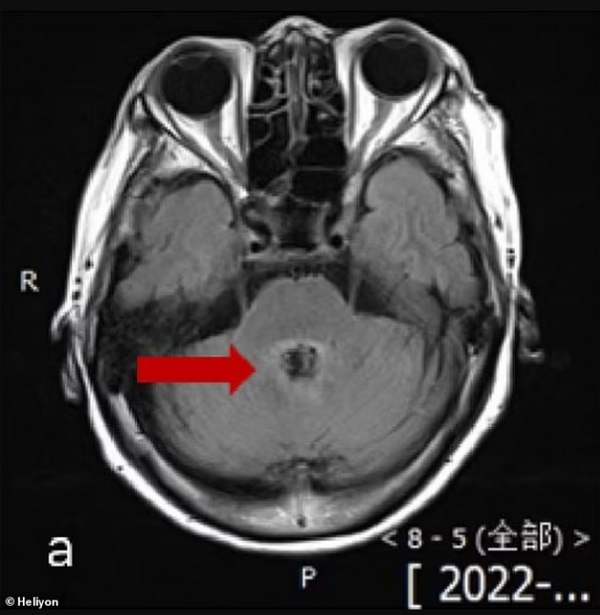

žalila se na vrtoglavicu, zbunjenost i teškoće u govoru. Lekari su mislili da boluje od tumora na mozgu jer su njeni skenovi pokazali leziju.

Međutim, lumbalna punkcija – kada se igla ubode u kičmu radi testiranja tečnosti – otkrila je da je zaražena Balamuthia mandrillaris, jednoćelijskim organizmom koji se širi na mozak i ubija devet od 10 pacijenata.